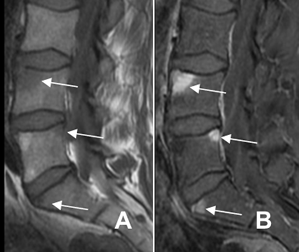

Fig 59 H. Espondilodisquitis.

A: RM sagital en T1 y B: RM sagital en T2. Erosión en la placa terminal inferior de L4, de bordes hiperintensos en ambas secuencias.

Fig 59 I. Espondilodisquitis.

A: RM sagital en T1 y B: RM sagital en STIR. Igual paciente anterior. Además de la erosión en la placa terminal inferior de L4, un año después, se identifica otra en L5. Tienen localización central y en ambos casos se aprecian cambios inflamatorios agudos.